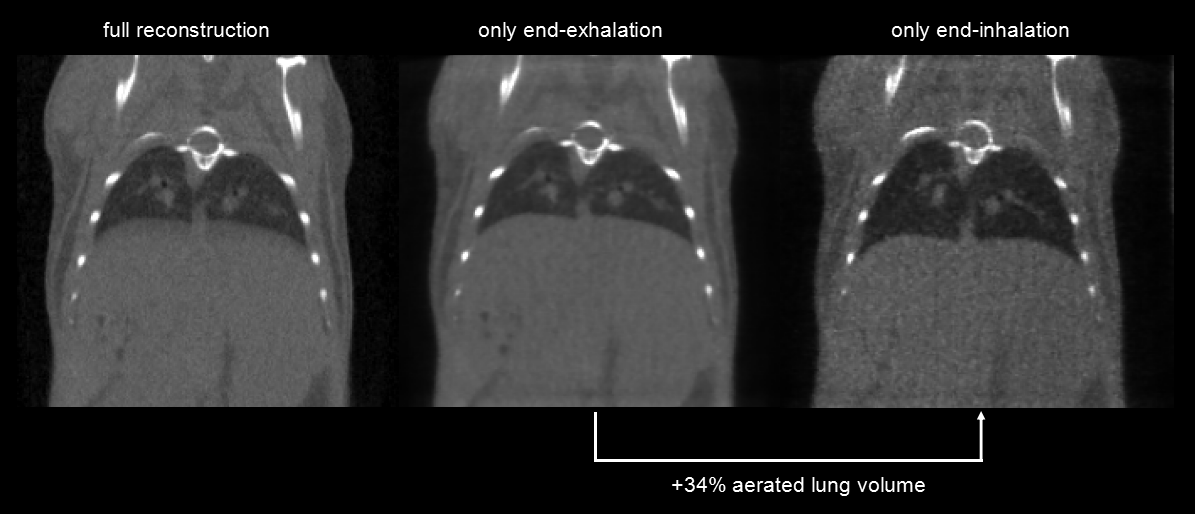

Respiratory gating: Ultra-high temporal resolution (10ms), 4min, 390mGy. Left: Integrated picture. Middle image: at the end of the exhalation and right image: at the end of the inhalation show a 34 percent difference in the volume of the lungs.